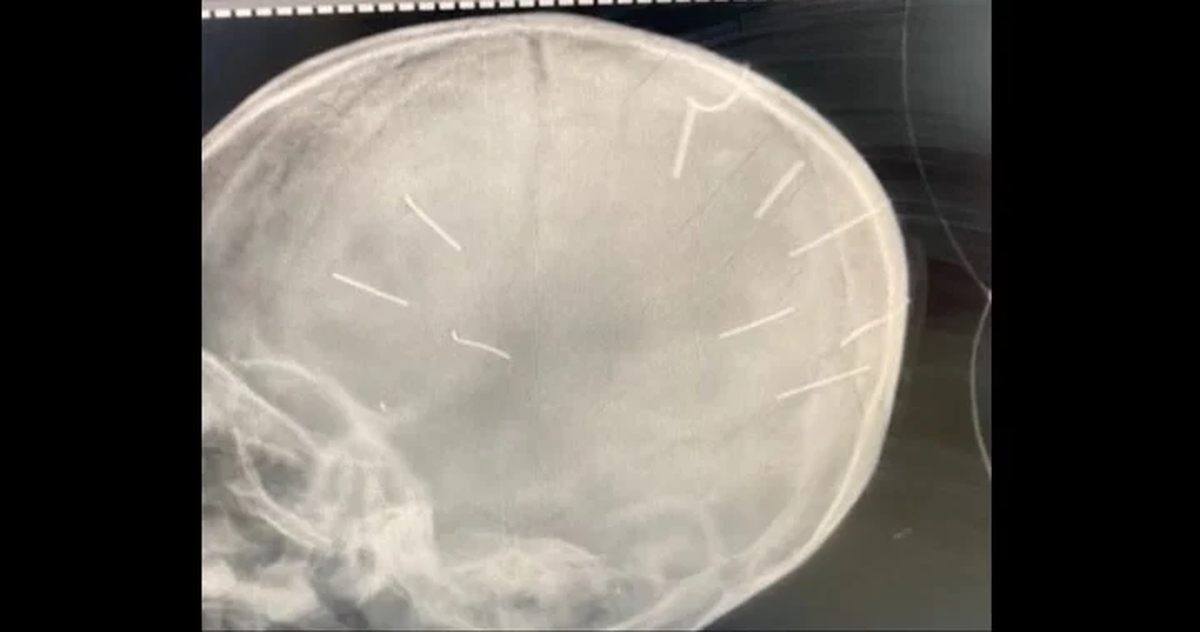

Tras el hallazgo del cuerpo, una rápida investigación policial descubrió el horror del crimen: en una imagen de rayos X del hospital Saint Paul se vieron las heridas de nueve clavos incrustados en su cráneo